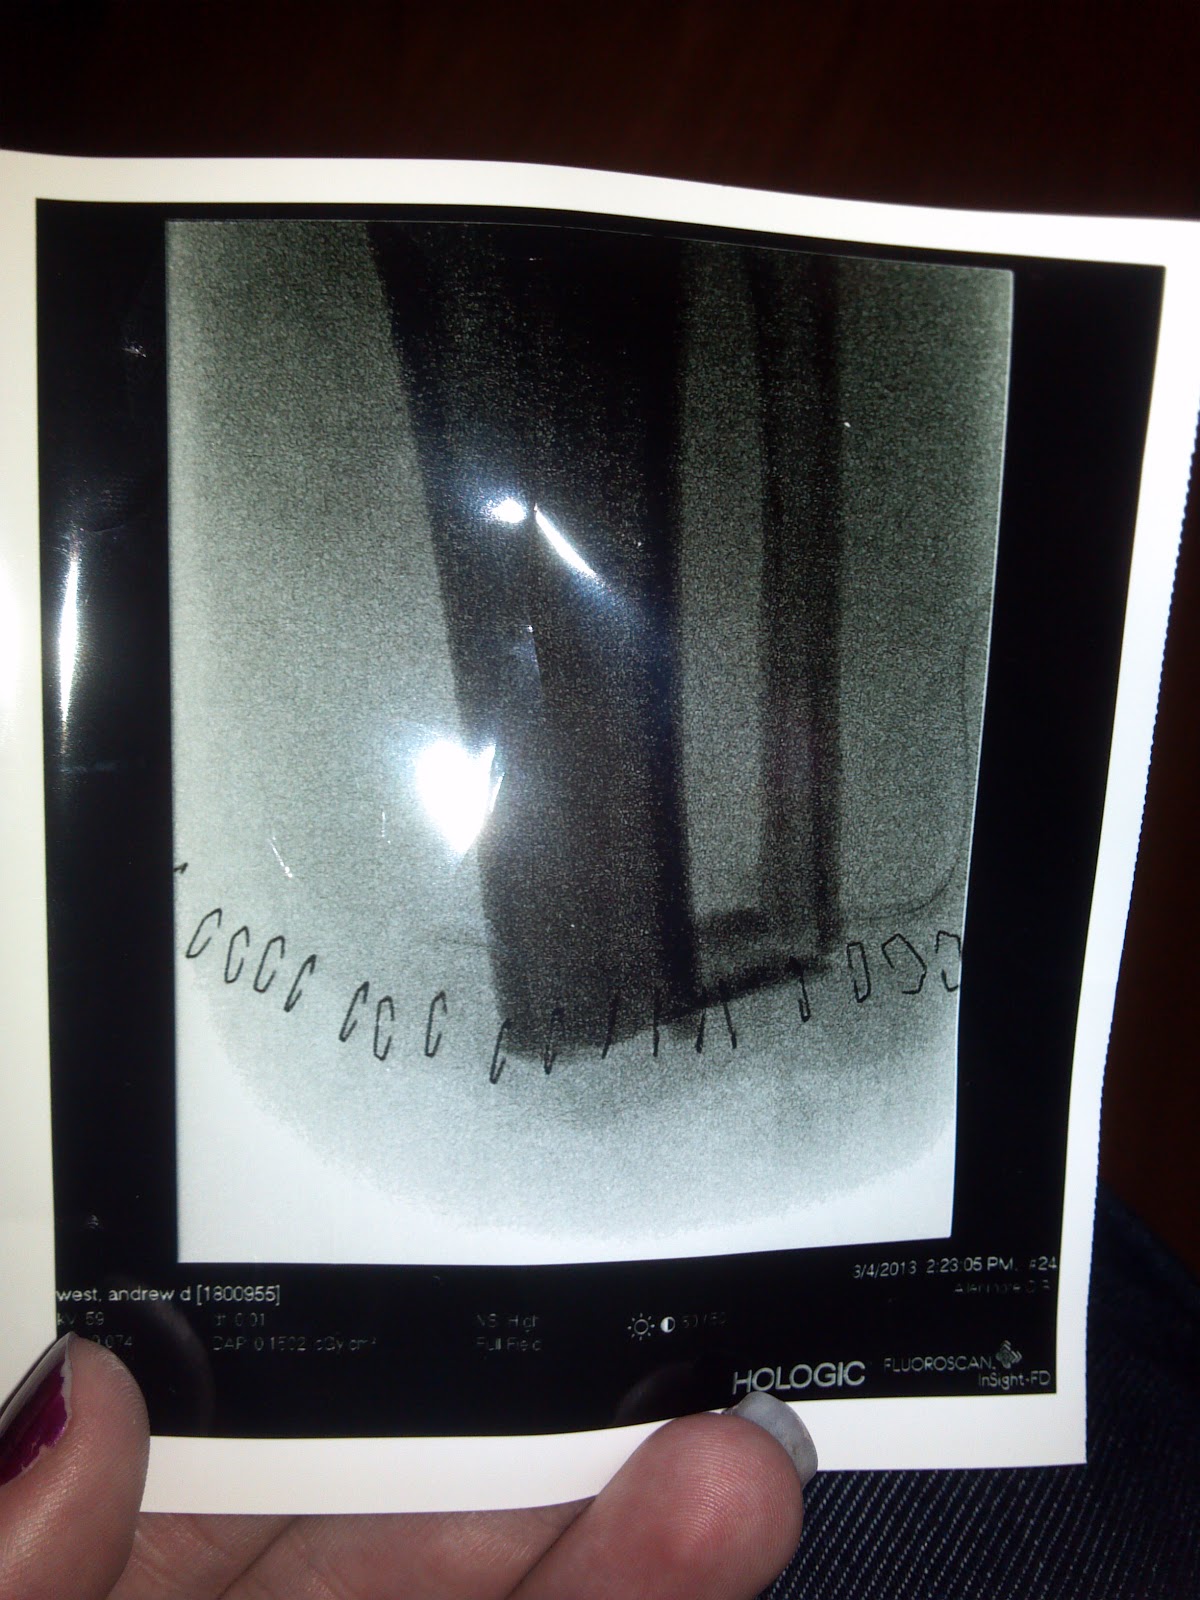

Today was possibly the worst day I have had in a long time. Nothing went well, remember that game chutes and ladders? Today was like that one giant chute that took you all the way back to the beginning from close to the end. It turns out that rain, trex decking, and crutches don’t work well together. I was crutching out of an establishment and I slipped and fell. Not thinking I tried to catch myself with a left foot that wasn’t there and with all my weight, stepped down, and smashed the crap out of my nub. In a ton of pain, Arianna rushed me to the Emergency Room. I sat there for a long while waiting to hear anything. Finally the doctor took x-rays and told me we needed to wait for Dr. Pakzad (my surgeon) to do anything. Getting out of surgery, Pakzad came into my room armed with a couple different size scalpels, scissors, tweezers, needles and many other medical instruments to complete his arsenal. I had two open wounds that, according to him, “didn’t look good”. So Without any more talk he grabbed his tools of his trade and started to cut, deeper and deeper he went cutting high and low removing anything that had grown in the last month. He cut everything out in order to remove any and all infection or dead tissue—making the wound essentially brand new. In doing this he almost doubled the size of each open wound. So what came next: a nice hot dish of disinfectant with sutures on the side. Three stitches came next and I tell you what, that was a cool thing to watch. Oh yeah and did I forget to mention he did all of this without anything to mask the pain, Strait up bite on a bullet status. I mean I have a pretty high pain threshold but COME ON!!!  After the fun stuff Doc told me I had broken everything in Sir Nubbers and I’m  back to square one. So my clock starts over. After going through this I was in a lot of pain and just wanted to get out of there. The doctor’s final words where “if that bone doesn’t heal up properly, we will have to put you under and take it out”. Awesome, if I don’t heal well, I have to get a surgery to undo what he already did.  So I can’t drink for another two months plus, I’m stuck in this stinking apartment and I’m in a ton of pain currently. Nothing is coming up Drew. So to all of my friends: Please come over more, I know I’m boring and kind of weird because I don’t see a lot of people anymore; but it means the world to me just having people in the same room as me. If you’re just doing homework or reading a book, or checking your fantasy baseball—I don’t care just kick it with me. If I don’t have friends by my side in this time, honestly, I might break. I need people. I love you all and I hope everything is going fantastic on your ends.